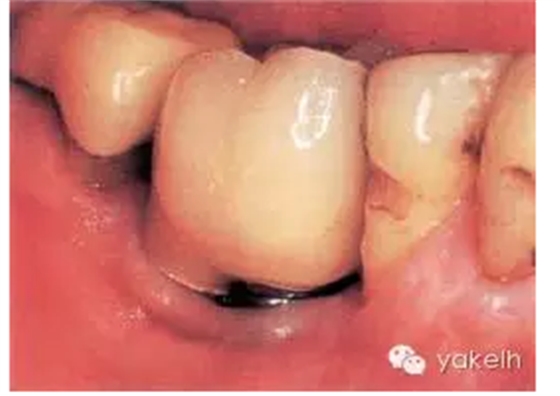

患者前牙3個(gè)單位的固定橋修復(fù),UR1和UL2為種植體(圖.7),存在美學(xué)問題。為了糾正修復(fù)位點(diǎn)的軟組織缺陷,修復(fù)體選用粉色瓷層,這樣可以調(diào)整牙齒的大小和外形。但是該病例左上兩種植體頸部金屬外露,周圍黏膜存在炎癥,同時(shí)種植體周圍軟組織下方透出灰色。

圖.7 修復(fù)體選用粉色齦層糾正了軟組織缺陷,種植體頸部暴露影響美觀效果。